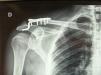

El control radiográfico anteroposterior de la articulación AC preoperatorio y postoperatorio (fig. 2) daba suficiente información para valorar pérdidas de reducción de la clavícula, el deterioro de la articulacón AC y la presencia de erosiones subacromiales debidas a la presencia del gancho. La media de retirada de la placa fue a las 9 semanas (rango de 6–12 semanas). El período de seguimiento medio fue de 6 meses (rango de 4–12 meses).

La media de la reincorporación a la actividad laboral fue completa en todos los casos a los 4,5 meses (rango de 2 a 9 meses). No se registraron secuelas ni incapacidad para realizar el trabajo previo al accidente. Todos, excepto uno de los pacientes, presentaban molestias durante la fisioterapia en abducción y antepulsión a partir de 90°, que desaparecieron al retirar la placa. Al paciente que no las presentó se le retiró la placa a las 12 semanas; uno de los objetivos de la retirada precoz era evitar las complicaciones consecutivas a la presencia del gancho. En 10 de los 11 casos no se dieron pérdidas de reducción tras la retirada de la placa. En el caso en que la hubo, fue parcial (fig. 3), en el último control radiográfico no había aumentado, no tuvo repercusión clínica ni retrasó la reincorporación del paciente a su actividad laboral.